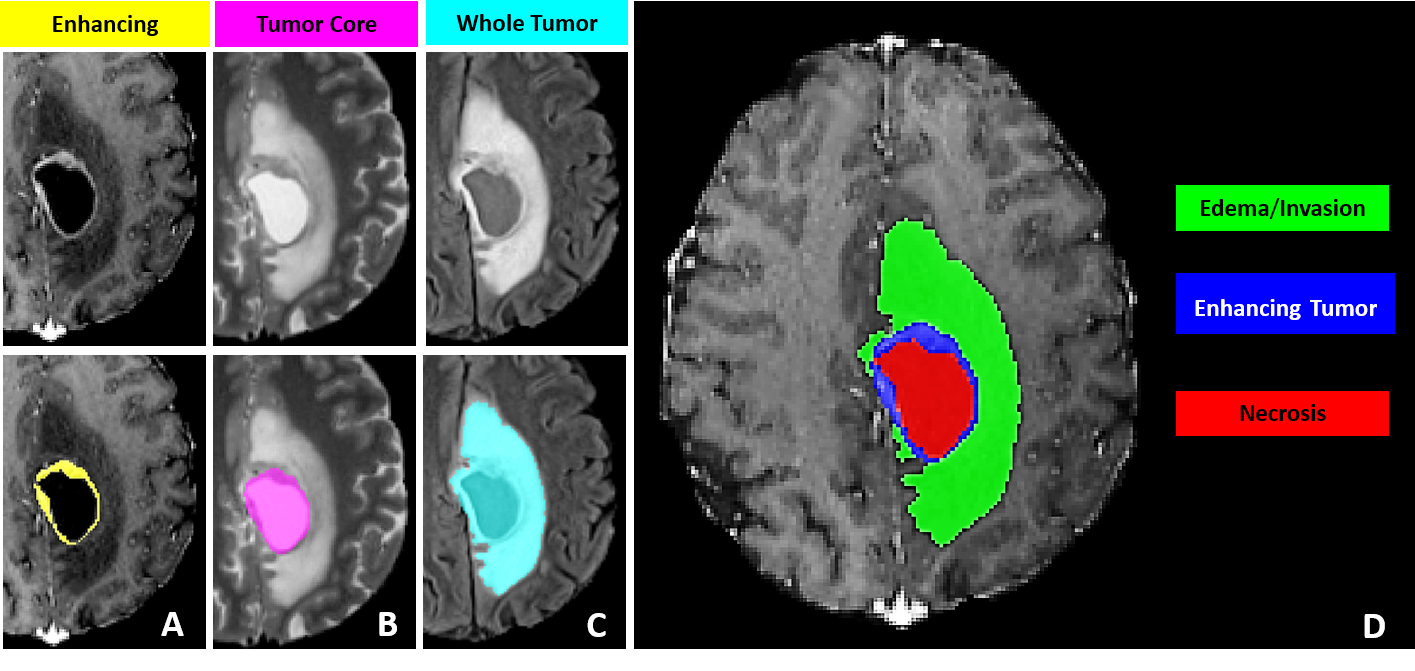

Consider brain tumor segmentation. The BraTS challenge requires annotators to delineate three tumor sub-regions (enhancing tumor, necrotic core, peritumoral edema) across four MRI sequences (T1, T1ce, T2, FLAIR) for every patient volume. A trained neuroradiologist needs 30 to 60 minutes per scan. A dataset of 1,000 volumes, which is modest by current standards, demands thousands of hours of expert annotation. Finding radiologists with free time is a problem that no model architecture can solve.

Swin UNETR (Hatamizadeh et al., 2022) replaces the convolutional encoder with a Swin Transformer for long-range spatial context through shifted-window self-attention. The decoder remains CNN-based with skip connections at multiple resolutions. On BraTS, Swin UNETR achieves competitive DICE scores with nnU-Net while capturing global context better, which helps with large diffuse structures like edema.